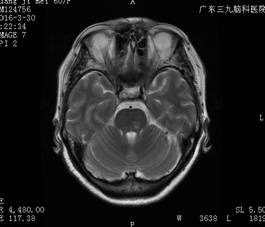

入院查体:左眼有光感,右眼视力:指距1500px;有脊髓炎病史。头颅MRI+增强提示:1.桥脑新增病变,结合病史,考虑视神经脊髓炎可能性大,医生建议补充全脊柱MRI平扫+增强扫描;2.左侧基底节区内囊后肢、右侧大脑脚多发小缺血灶同前;3.脑白质轻度变性同前(图一)。

图一